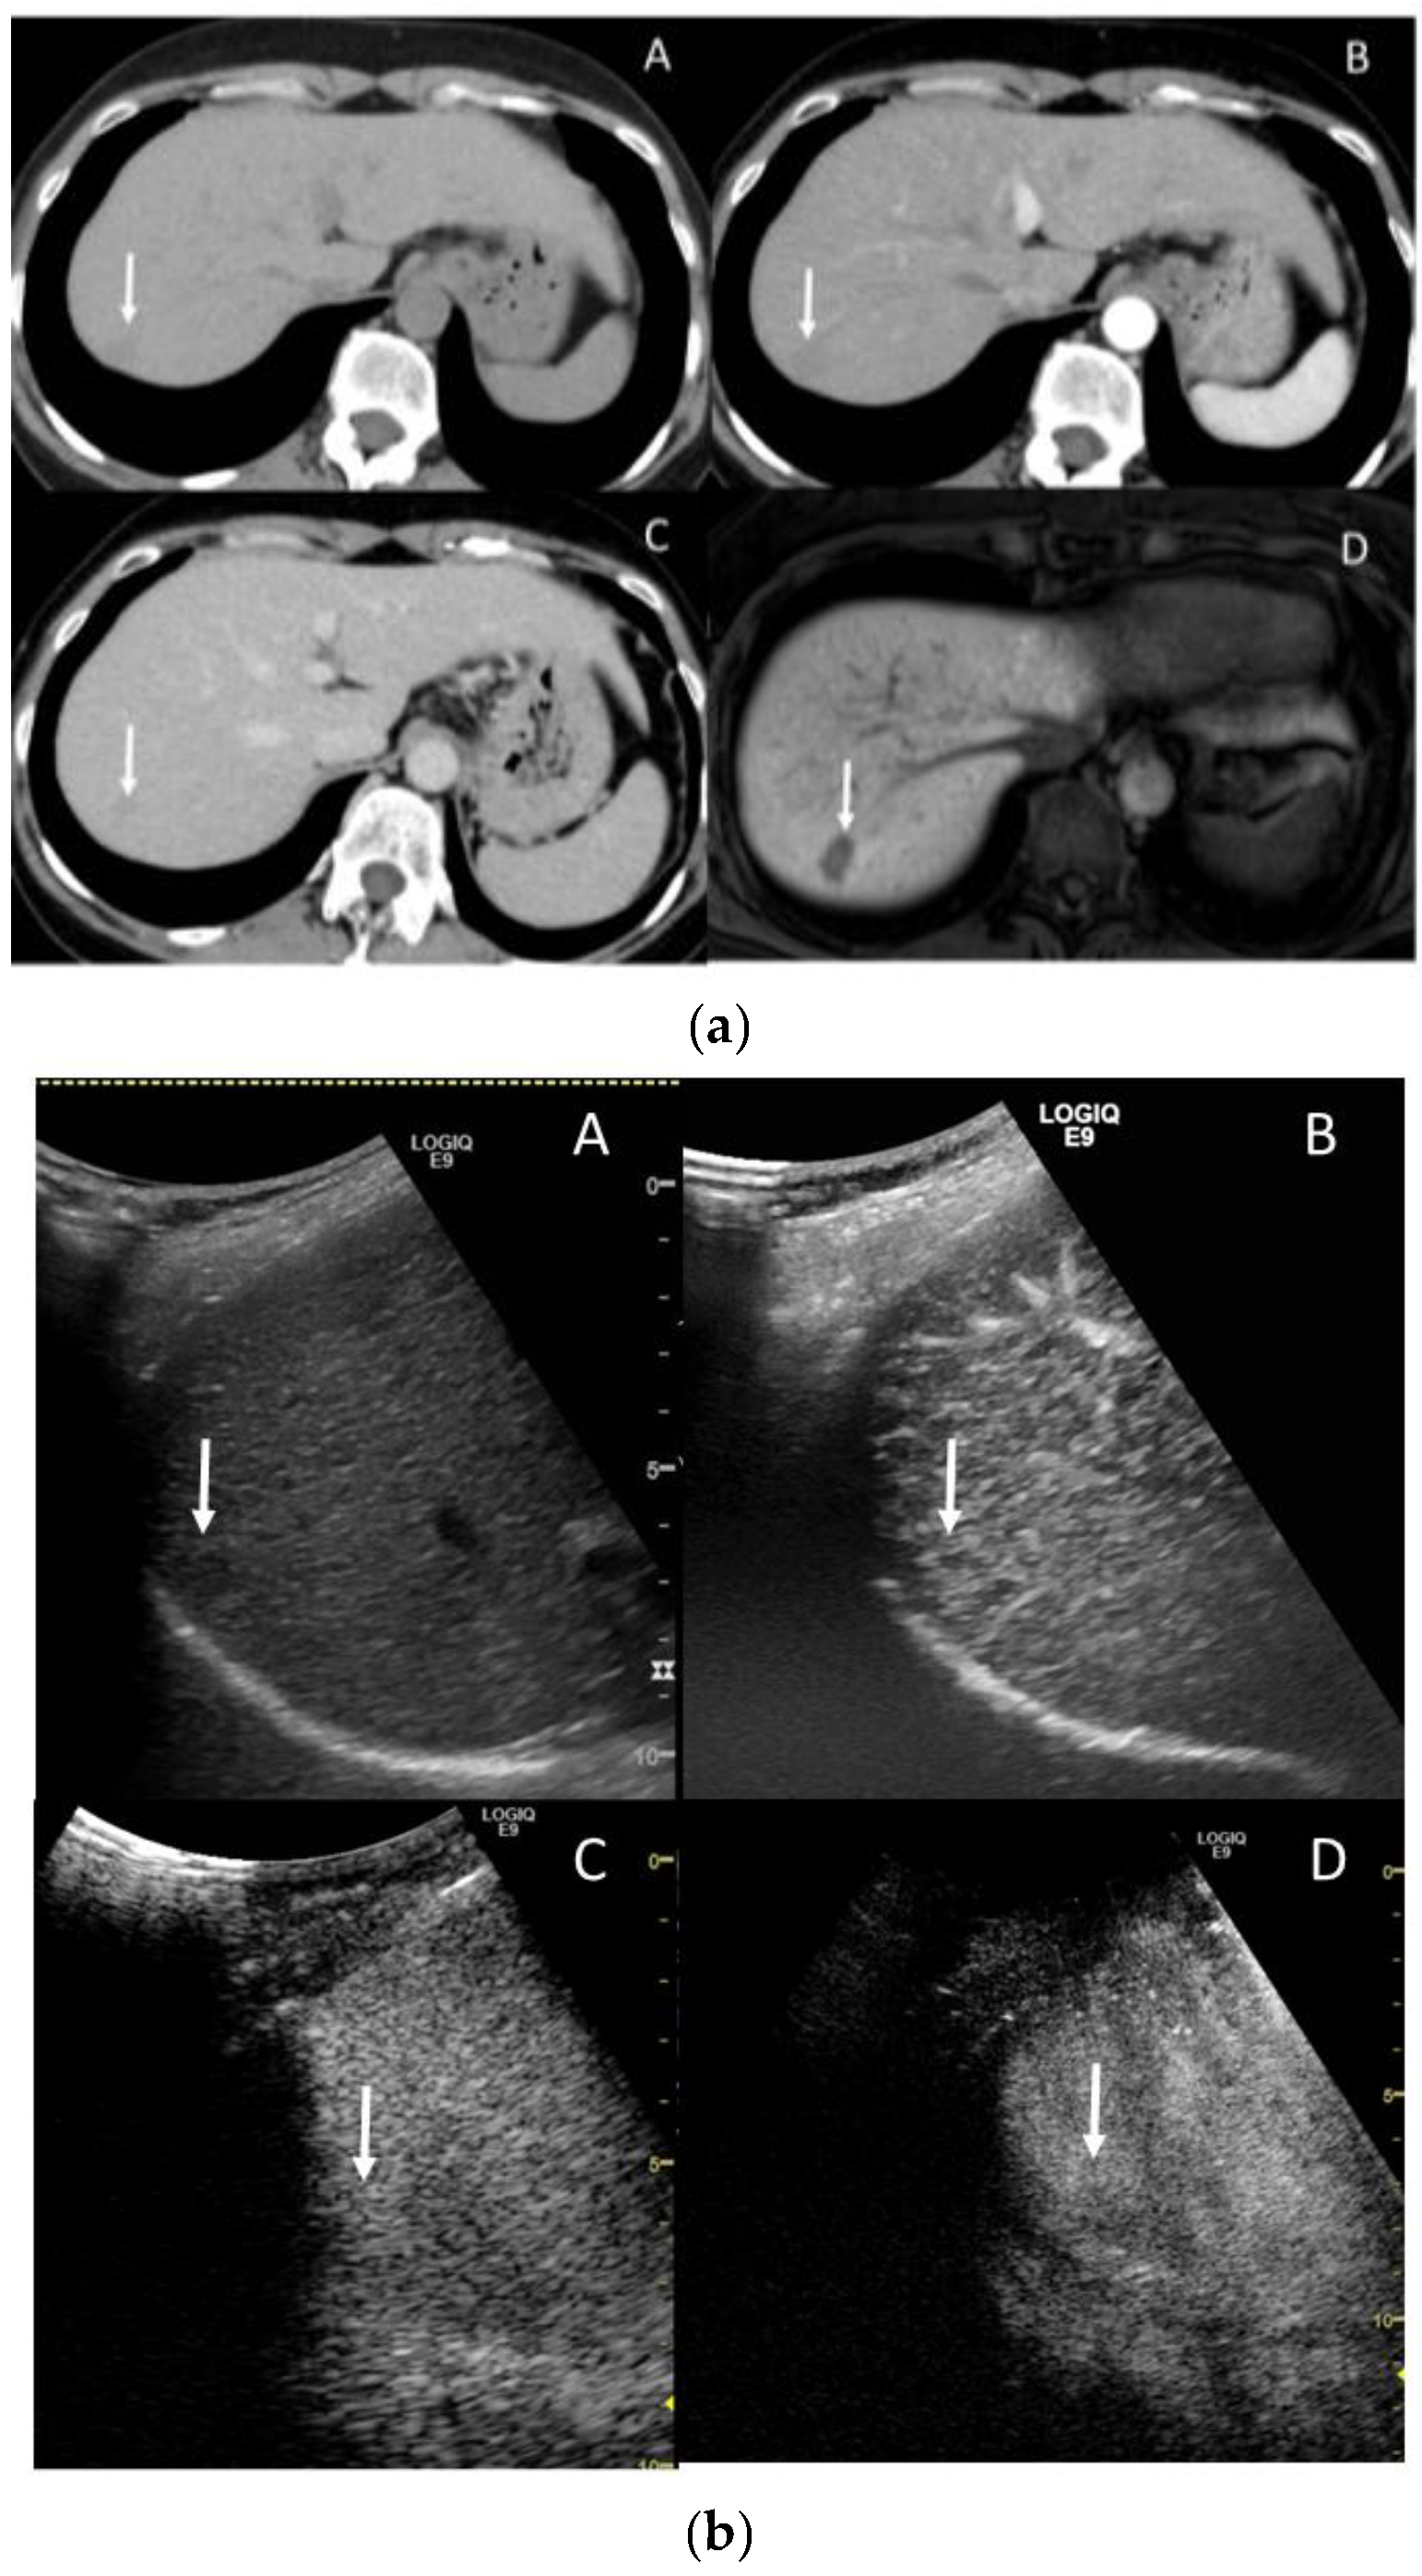

3.4. Extracellular Volume Fraction (ECV)

3.5. Extracellular Volume Fraction (ECV)

3.6. Gadoxetic Acid Enhanced MRI (EOB-MRI)